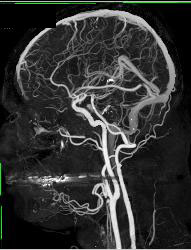

Normal Circle of Willis